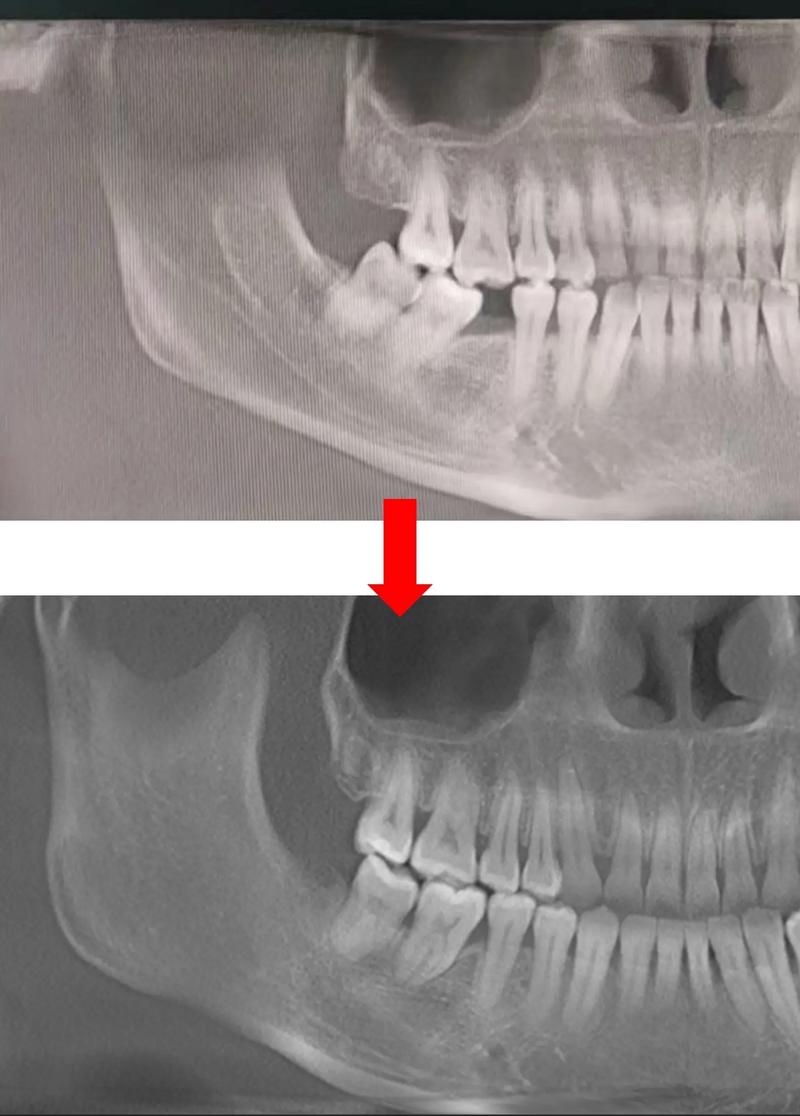

- 影像学检查: 拍摄全景片(曲面断层片)和CBCT(锥形束CT)是必须的! CBCT能清晰显示智齿的精确位置、方向、牙根形态、数量、弯曲度、与下颌神经管的关系以及缺牙区牙槽骨情况,这是制定方案和评估风险的关键。